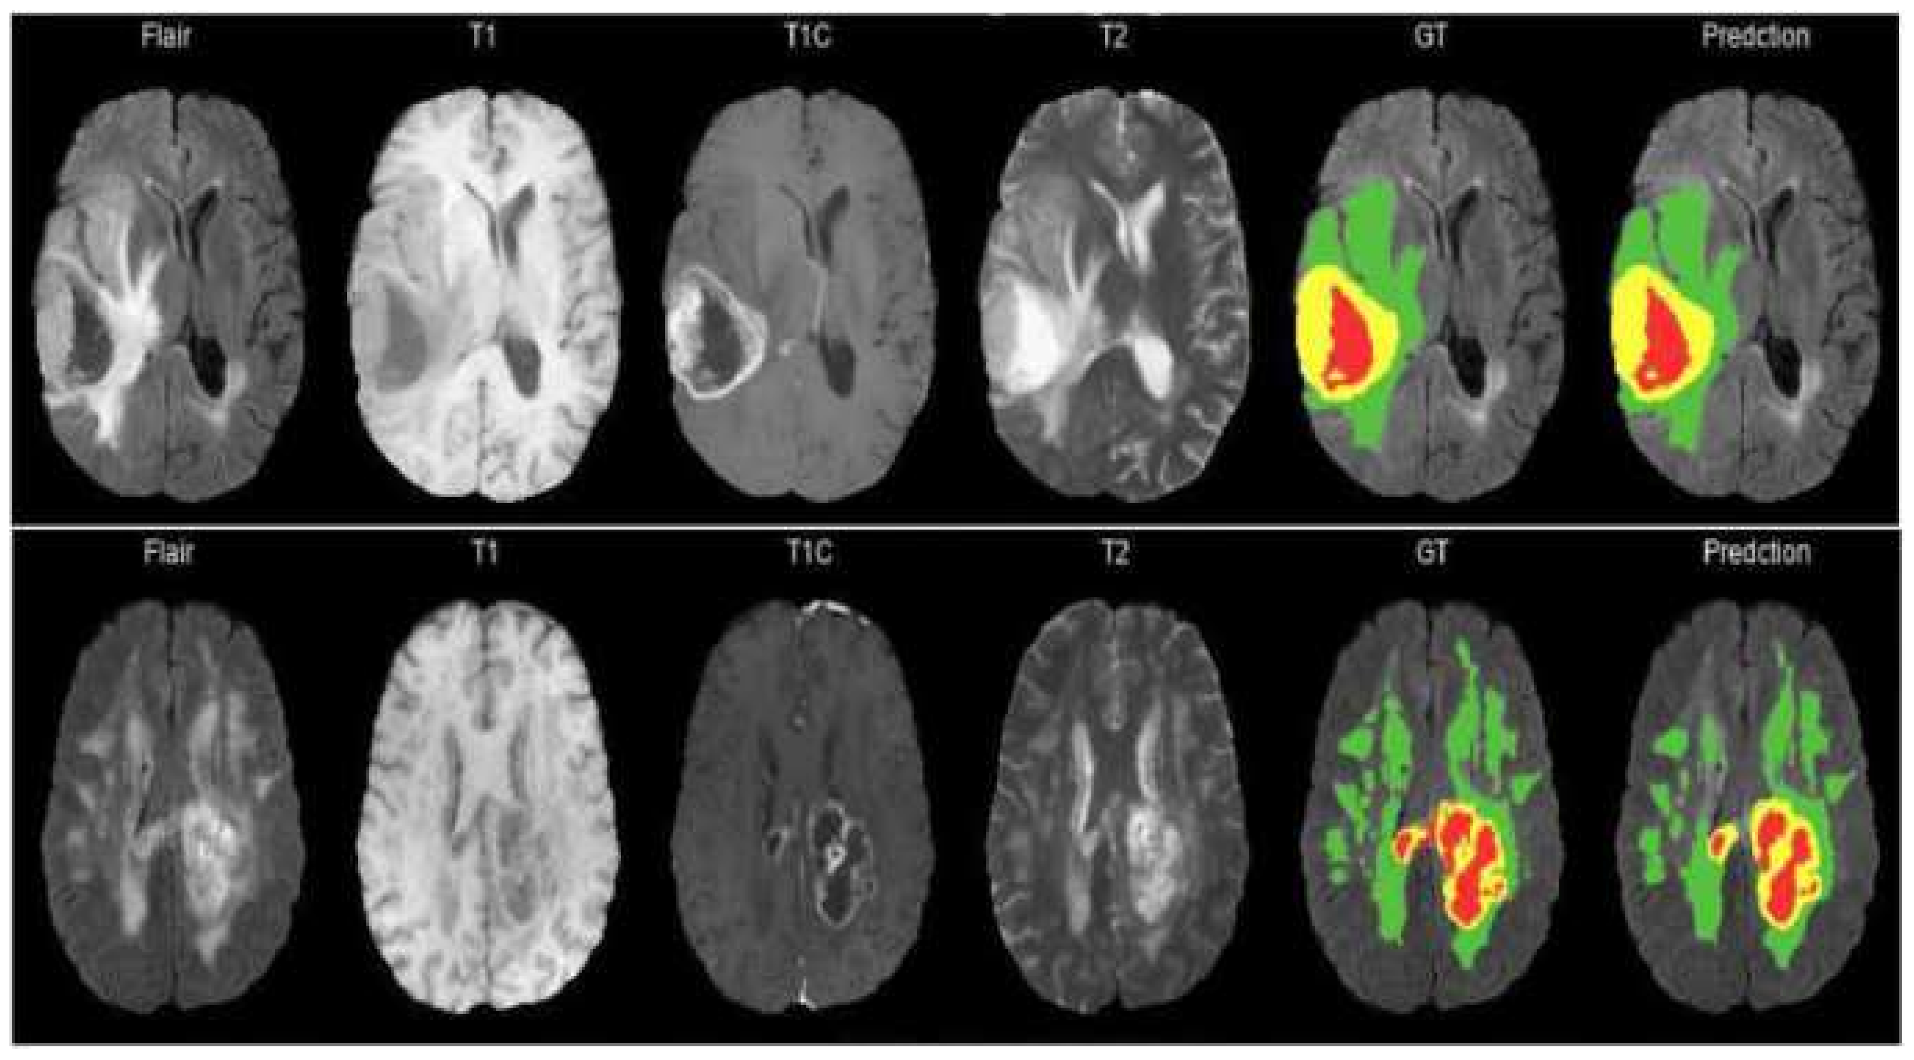

The BraTS 2020 dataset [22,23,24,25] is used in this research to evaluate the performance of the proposed network. There are 369 training, 125 validation, and 169 test multi-modal brain MR studies.T1-weighted (T1), post-contrast T1-weighted (T1ce), T2-weighted (T2), and fluid-attenuated inversion recovery (Flair) sequences are included in each study, as shown in Figure 4. The size of all the MR images is 240 × 240 × 155. In addition, experts annotated the enhancing tumor (ET), peritumoral edema (ED), as well as the necrotic and non-enhancing tumor core (NET) for each study. For online evaluation and final segmentation competition, the annotations for training studies are made public, whereas the annotations for validation and test trials are kept withheld.

Figure 4. MRI images and their ground truth for various modalities. Green, red, and yellow highlight the ED, NET, and ET areas, respectively.